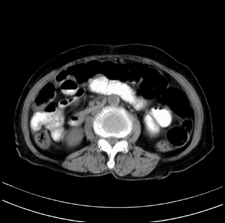

患者,女,75岁。腹痛,体黄5日,膝胸位时腹痛缓解。肝功能明日出来。彩超提示胆总管占位,未见血流信号。心电图提示s-t段改变。患者体质较弱,未能增强。

胆总管结石

胆总管多发结石

胆总管多发结石伴肝内外胆管轻度扩张。

胆总管上段,腔内有软组织密度影 ,ct值36-44hu。大家看有没有胆管癌的可能。

典型胆总管多发结石;增强扫描前后ct值是否发生改变是鉴别结石与占位的依据。